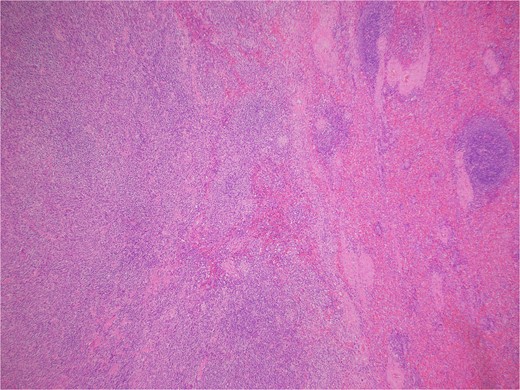

Histologic sections revealed spleen with partial effacement of tissue architecture by a well-circumscribed, nonencapsulated mass (Fig. 3) displaying mixed inflammatory elements, including scattered reactive-appearing lymphoid cells with a vague nodular appearance, plasma cells, histiocytes, and giant cells. Variably increased stromal/spindled cells were noted throughout (Fig. 4). The background splenic architecture appeared unremarkable.

Variably increased stromal/spindled cells were noted (hematoxylin & eosin 400X).